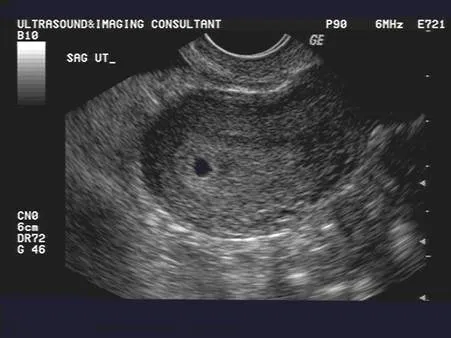

剛懷孕從陰道超音波照出來的妊娠囊(圖片取自網路:https://www.fetalultrasound.com/online/text/3-034.htm)

上一篇說過的,懷孕從最後一次月經的第一天就開始算了,所以通常會驗孕的時間,都是下一次月經沒來的時候,也就是懷孕四週囉!不過這個時間點,比較尷尬,就是妊娠囊(gestational sac)有機會看的到,也有可能看不到的時候。所謂的受精卵看起來就像下面這樣子。

因為常規估算妊娠週數的方法會用妊娠囊平均直徑MSD(mean sac diameter)加上4來計算(欸?)。對!沒錯喔,回推起來就是在若有似無之間。因此,要更確定看的到,個人認為,可以再過一個禮拜左右,也就是大概五週的時後再來看看,這個時候比較不會照不到,進而造成媽媽們的緊張和困擾。